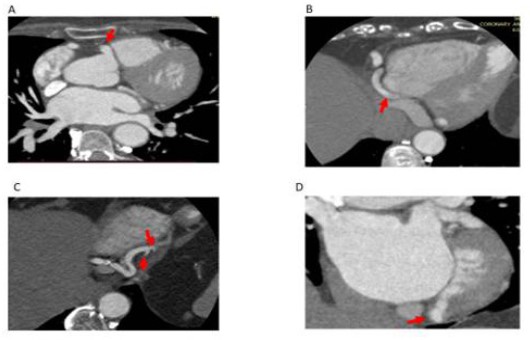

Coronary cameral fistula in a 57-year-old female patient presented with chest pain. (a) Axial CT coronary angiogram images show a right coronary artery originating from the right sinus of Valsalva (arrow in a) coursing into the atrioventricular groove (arrow in b) with a subsequent bifurcation forming the posterior descending artery (PDA) (curved arrow in c) and Posterior Left Ventricular branch (PLV) (arrow in c). PLV is draining as coronary cameral fistula into the left ventricle chamber (arrow in d).

Figure 1: